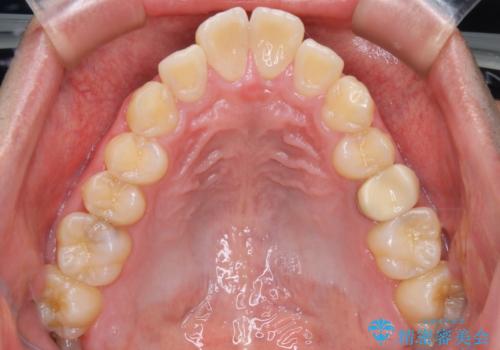

- 上顎前歯の突出感と下顎前歯のガタつきが主訴で来院されました。

出っ歯とガタつきの改善を行うには抜歯が必要と診断し、上下左右第一小臼歯を抜歯する計画を立てました。

抜歯する事で歯の移動量が大きいことからワイヤー表側矯正装置で治療を行うことになりました。